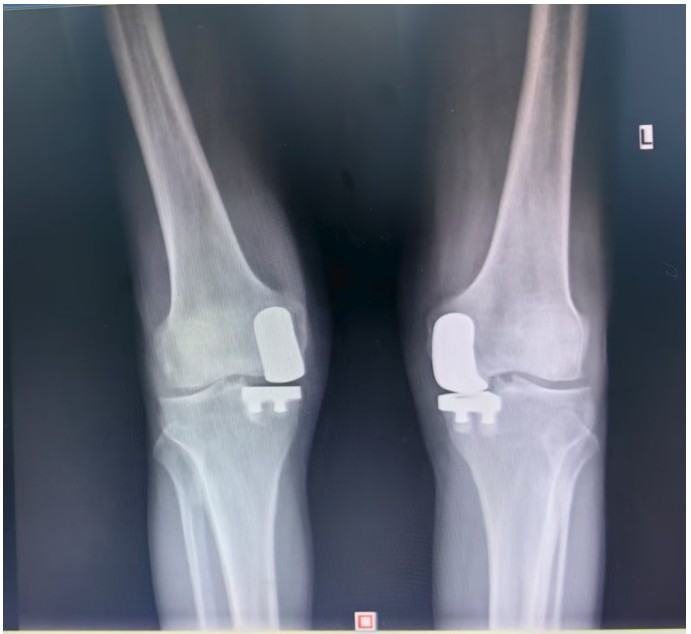

通訊員王珂報(bào)道:近日,一位來自江西的大爺跨越六百公里,專程來到衡陽市中心醫(yī)院關(guān)節(jié)外科求診。羅湘平主任醫(yī)師、彭健副主任醫(yī)師團(tuán)隊(duì)熱情地接待了患者,并成功為其實(shí)施了“雙側(cè)人工膝關(guān)節(jié)單髁置換術(shù)(UKA)”。術(shù)后膝關(guān)節(jié)功能顯著改善,第二天便可下地活動(dòng),雙側(cè)膝關(guān)節(jié)活動(dòng)度輕松達(dá)到90°,對(duì)手術(shù)效果非常滿意,已于9月10日順利出院。

據(jù)了解,患者1年前無明顯誘因出現(xiàn)雙膝關(guān)節(jié)疼痛,以右側(cè)膝關(guān)節(jié)為主,近5個(gè)月來雙膝關(guān)節(jié)疼痛明顯加重,不但日常行走困難,生活質(zhì)量更是受到極大影響。經(jīng)多家醫(yī)院治療效果均不理想,了解到衡陽市中心醫(yī)院關(guān)節(jié)外科在關(guān)節(jié)置換領(lǐng)域擁有豐富的臨床經(jīng)驗(yàn)和良好的患者口碑,毅然決定赴衡求醫(yī)。醫(yī)生發(fā)現(xiàn)患者雙膝關(guān)節(jié)已有內(nèi)翻畸形,關(guān)節(jié)內(nèi)側(cè)骨性膨大,X線提示雙膝退行性病變,雙膝內(nèi)側(cè)間隙明顯狹窄,手術(shù)為最佳治療方式。為了達(dá)到根治目的,羅湘平主任醫(yī)師、彭健副主任醫(yī)師為患者進(jìn)行了詳細(xì)查體及綜合評(píng)估,術(shù)前組織開展多學(xué)科討論(MDT)。考慮到易叔叔的膝關(guān)節(jié)骨關(guān)節(jié)炎僅局限于內(nèi)側(cè),外側(cè)間室軟骨良好,若采用全膝關(guān)節(jié)置換術(shù)會(huì)將失去正常關(guān)節(jié)間室的軟骨與韌帶,創(chuàng)傷較大,便為其制定了右膝關(guān)節(jié)單髁置換手術(shù)治療方案。在充分完善術(shù)前準(zhǔn)備后,羅湘平主任、彭健副主任醫(yī)師團(tuán)隊(duì)為患者實(shí)施了右側(cè)膝關(guān)節(jié)單髁置換術(shù)。手術(shù)過程順利,團(tuán)隊(duì)?wèi)?yīng)用微創(chuàng)術(shù)式(MIS)及“精準(zhǔn)間隙平衡技術(shù)”,最大程度減少了手術(shù)創(chuàng)傷,為術(shù)后快速康復(fù)奠定了堅(jiān)實(shí)基礎(chǔ),術(shù)后第二天即可借助助行器下地活動(dòng)。6天后團(tuán)隊(duì)順利為患者實(shí)施了左側(cè)膝關(guān)節(jié)單髁置換手術(shù)。目前,易叔叔在關(guān)節(jié)外科醫(yī)護(hù)團(tuán)隊(duì)的精心指導(dǎo)和康復(fù)治療下,恢復(fù)情況良好,雙側(cè)膝關(guān)節(jié)活動(dòng)度輕松達(dá)到90°,膝關(guān)節(jié)功能顯著改善,能夠獨(dú)立下地行走,對(duì)手術(shù)效果非常滿意,已于9月10日順利出院。